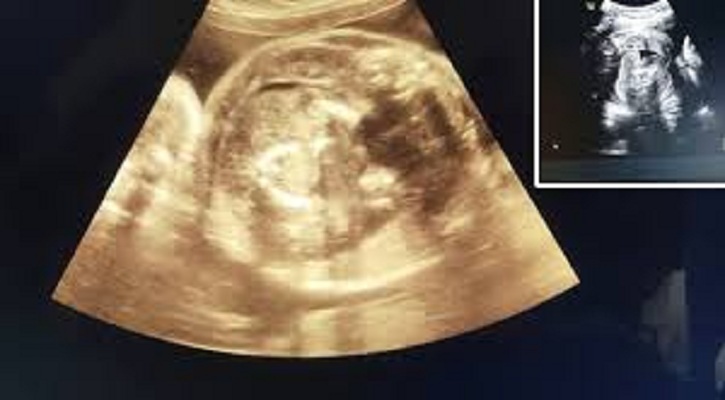

প্রসঙ্গত, 'ভ্রূণের মধ্যে ভ্রূণ'-এর উপস্থিতি অত্যন্ত বিরল ঘটনা। গবেষণা অনুযায়ী, গোটা বিশ্বে এমন ঘটনা পাঁচ লাখে একটি। বুলধানা জেলায় ৩২ বছরের ওই নারী তার গর্ভাবস্থার অষ্টম মাসে সোনোগ্রাফি করাতে সরকারি হাসপাতালে এসেছিলেন।

সেই সময় পরীক্ষা করে জানা যায়, ওই নারীর গর্ভে যেমন একটি শিশু রয়েছে, তেমনই ওই শিশুর গর্ভেও একটি ভ্রূণ রয়েছে। বিষয়টি সম্পর্কে নিশ্চিত হতে চিকিৎসক এবং বিশেষজ্ঞদের একটি টিম আরও একবার সোনোগ্রাফি করেন।

তখনও গর্ভে থাকা শিশুটির গর্ভে একটি ভ্রূণ স্পষ্টভাবে দেখা যাচ্ছিল। বুলধানা জেলা সরকারি হাসপাতালের শল্যচিকিৎসক (সিভিল সার্জন) ডা. ভাগবত ভুসারি বিবিসি মারাঠিকে এই ঘটনার কথা জানিয়েছেন।

ডা. ভুসারি বলেছেন, "সোনোগ্রাফি পরীক্ষার পর দেখা যায়, ওই নারীর গর্ভে একটি শিশু রয়েছে এবং শিশুটির গর্ভে আরও এক শিশু রয়েছে। তবে একে ঠিক শিশু বলা যাবে না, কারণ এটি ফিটাল মাস। এক অর্থে বলতে গেলে, এটি একটি মাংসের পিণ্ড।"

"এটি জীবিত শিশু নয়, কারণ তার হৃদস্পন্দন নেই। দেখতে শিশুর মতো মনে হয় বলেই একে বেবি বলা হয়।"

বিষয়টিকে আরও বিশদে ব্যাখ্যা করেছেন তিনি। ডা. ভুসারির কথায়, "ওই মাংসপিণ্ড আকারে বৃদ্ধি পাচ্ছে, কারণ সেখানে রক্ত সরবরাহ অব্যাহত রয়েছে। ডাক্তারি ভাষায় একে ফিটাস ইন ফেটু (ভ্রূণের অভ্যন্তরে ভ্রূণ) বলা হয়।"